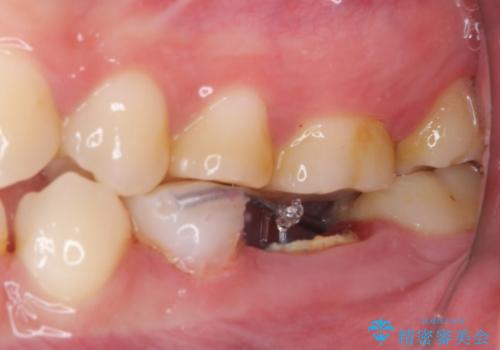

- クラウンを装着したばかりの歯の歯肉が腫れていることを気にして来院された患者様です。

むし歯がとても大きく、歯茎に歯の一部が埋もれてしまっているため、汚れが溜まりやすくなっている状態でした。

根歯の挺出(歯を引っ張り出す部分矯正)、歯周外科処置などを行った後、オールセラミッククラウンにて補綴することとしました。